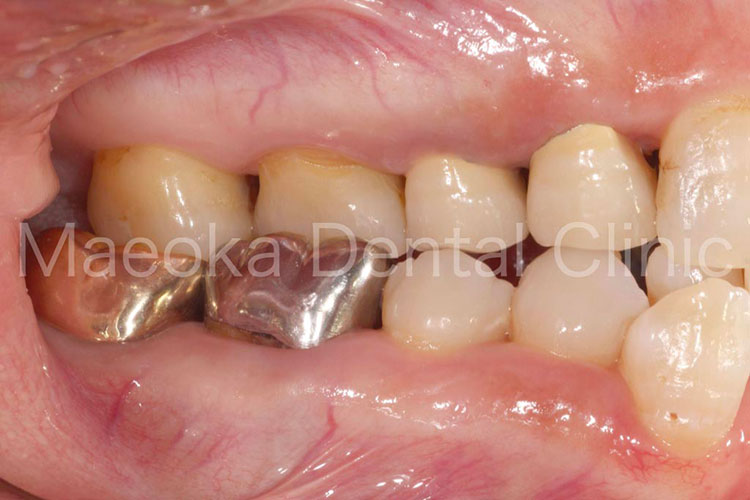

Case4

患者さんは58歳の男性の方で、「右下の歯がグラグラして痛いので診て欲しい」という主訴で来院されました。お口の中を拝見すると重度の歯周病を認めました。1日1箱近い本数の喫煙があったこともあり、歯肉は血行不良を起こして黒っぽい印象がありました。

初診時には歯周病の原因と「どうすれば歯周病は治るのか」、「再発を防ぐためには何が必要なのか」を説明し、歯磨きのトレーニングをスタートしました。その後、患者さんのプラークコントロールレベルが向上したタイミングで歯石を取り、基本治療を終えました。その後、義歯を入れるなどの機能回復も検討しましたが、患者さん自身が不都合を感じていなかった点、レントゲン上でも残存歯の負担が増加している所見が見られなかった点を考慮し、経過観察としています。

主訴の右下7は失うことになってしまいましたが、その他の歯は現在のところ1本も失うことなく経過しています。現在も喫煙はありますが、歯肉は引き締まり、健康な組織を取り戻しています。今後はメインテナンスを通してプラークコントロールレベルの維持に患者さんと取り組んでいきます。

初診時の右下大臼歯部

右のボタンをクリックすると表示されます。

治療前(正面)

治療後(正面)

治療前(右側方面)

治療後(右側方面)

治療前(左側方面)

治療後(左側方面)

治療の詳細解説